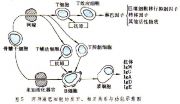

| 2021年7月26日 (一) 20:01 | 两种淋巴细胞的发育关系功能示意图.jpg (文件) |  |

39 KB | 77921020 | Uploaded with SimpleBatchUpload | 3 |